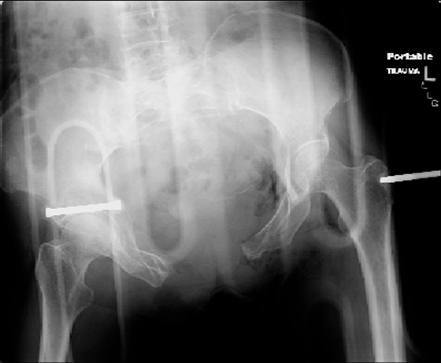

Отправитель: dan schlatterer 12 Июнь 2007, 04:47

attached are several CT cuts. please let me know if you need more. the CT is pre-pelvic ex-fix placement.

Thank you.

Отправитель: Chip Routt 12 Июнь 2007, 04:53

I wouldn't plate the front.

But I would add screws posteriorly.